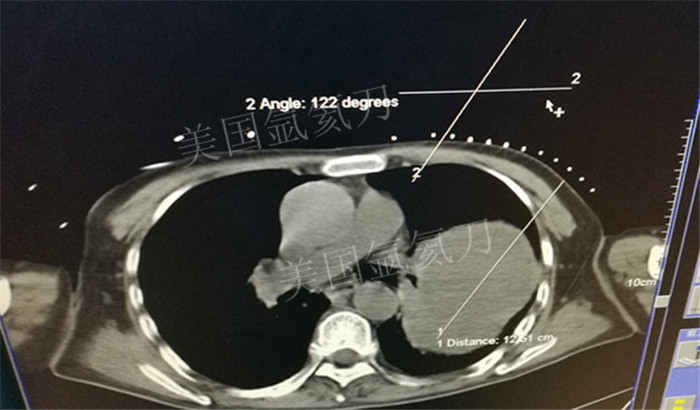

下一篇:氩氦冷冻治疗最大径8.2肿瘤,冰球最大径7.9